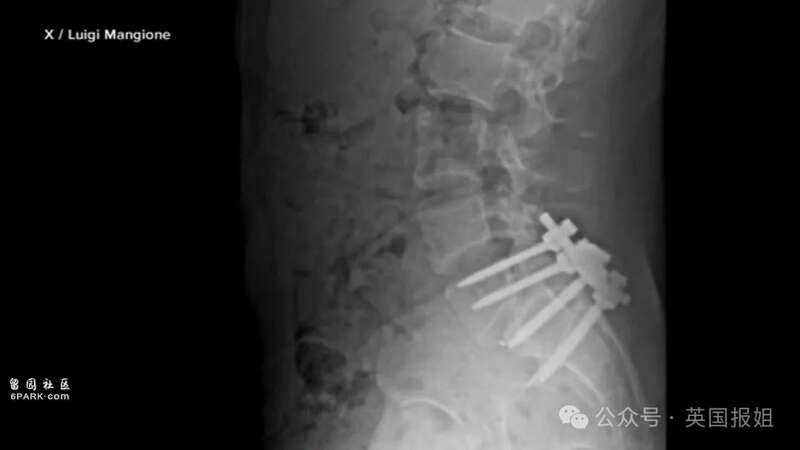

曼焦内虽出身于富裕家庭,但在背部受伤后,与医疗保险公司交涉过程中,被拖延的不公正待遇激起了他对整个系统的愤怒。